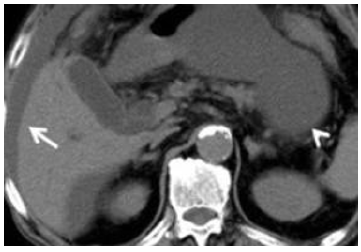

Intrapancreatic Accessory Spleen Masquerading as a Neuroendocrine Tumor

Yassine Zerhari, Hatim Essaber, Mohammed Ennmer, Asaad El Bakkari, Soukaina Allioui, Hounayda Jerguigue, Youssef Omor and Rachida Latib. 10(7):03-05.